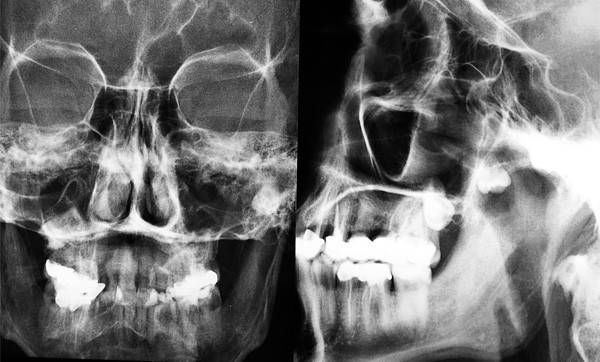

Un patient âgé de 38 ans nous est adressé par son médecin traitant du fait de la survenue d’épisodes de trismus à répétition, évoluant favorablement sous traitement antibiotique. Le praticien a demandé une radiographie face, profil, et un panoramique (OPT). Le patient présente un bon état général. L’examen clinique endobuccal est possible du fait de l’ouverture buccale à 30 mm. Il n’existe ni lésion de la muqueuse buccale, ni dentaire, ni adénopathie cervicale. L’interrogatoire ne rappelle pas de tentative d’avulsion de dent de sagesse.

1. Quelles sont les propositions exactes au vu du panoramique et des clichés de face et de profil (fig. 1a et b)

a. 28 incluse en position ectopique

b. 38 incluse en position ectopique

c. 18 incluse

d. Lésion kystique maxillaire gauche intrasinusienne